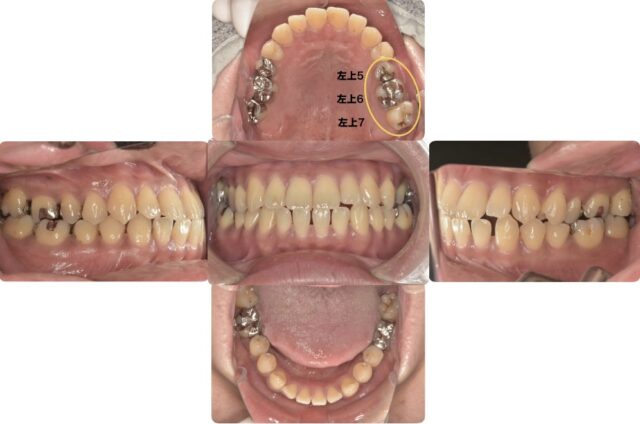

今回の部位は左上5、6、7です。

5番目と6番目にはメタルインレー、7番目にはCR(レジン)が詰められています。

その中でも6番目の歯の補綴の形に注目してください。前側と後ろ側がどちらも覆うような形状をしています。

これは補綴を作る上では禁忌の形状と言われている「MODインレー」です。

M▶近心(歯の前側)

O▶咬合面(歯の噛む面)

D▶遠心(歯の後ろ側) という意味です。